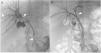

A 51-year-old man was evaluated for obstructive jaundice associated with mild dyspepsia. He had an unremarkable past medical history and physical examination revealed no significant findings except for jaundice. Laboratory test results showed altered liver enzymes (total bilirubin 20.1mg/dl, direct bilirubin 18.8mg/dl, AST 53U/l, ALT 144 U/l, GGT 386 U/l, ALP 203 U/l). A computed tomography (CT) scan and subsequent magnetic resonance cholangiopancreatography (MRCP) demonstrated a 1.2cm hilar mass, which constituted hilar stricture and occlusion of the biliary tract and its dilation in the intrahepatic area (fig. 1), suggesting hilar cholangiocarcinoma (Bismuth-Corlette II). Percutaneous cholangiography for internal-external biliary drainage confirmed the hilar stricture (fig. 2A); cholangiography performed 10 days later showed its normalization (fig. 2B). The patient underwent cholangioscopy that confirmed a normal biliary duct at the hilum (fig. 3) and endobiliary forceps biopsies were taken in the same session. The histopathologic evaluation revealed transmural chronic inflammatory cell infiltrates, with no signs of malignancy. Immunohistochemical staining showed IgG4-positive plasma cells (figs. 4 A and B). MRCP at 6 months confirmed a normal biliary tree (fig. 5).